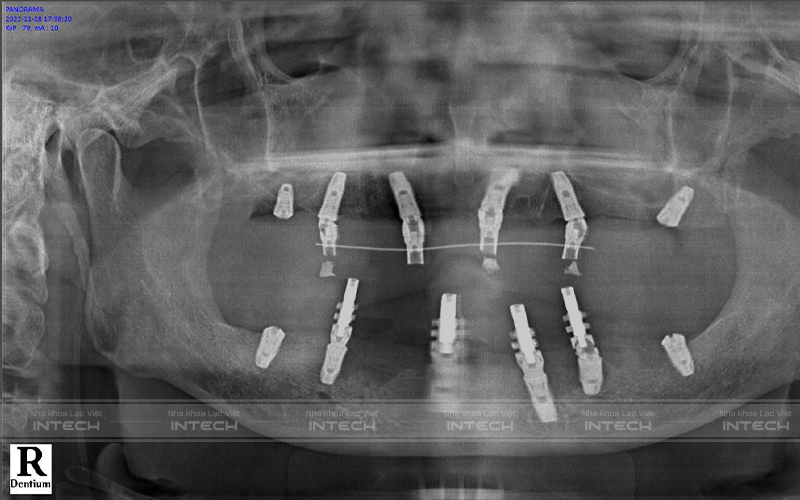

Ảnh chụp phim của chú Tuấn sau khi cắm trụ implant

Nhờ việc ứng dụng công nghệ Safe-tech trong quy trình trồng răng implant, kế hoạch điều trị của chú Quý được lên một cách chính xác. Vị trí đặt implant được xác định tại nơi có nhiều tế bào gốc và tránh các dây thần kinh, xoang hàm, giúp quá trình cấy ghép diễn ra an toàn, không đau, nhanh lành thương.